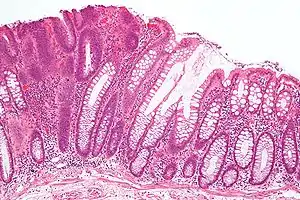

![]() Мікрофотознімок аденоми товстого кишечника (Г&E). Мікрофотознімок аденоми товстого кишечника (Г&E). | |